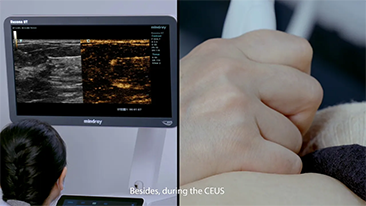

?QuĂ© tan claramente se puede ver un hĂgado?

Para las lesiones hepĂĄticas focales, como el hemangioma o el cĂĄncer de hĂgado, el diagnĂłstico por imĂĄgenes mediante ecografĂa con contraste cumple un papel importante. La tecnologĂa de diagnĂłstico por imĂĄgenes con contraste UWN+ (no lineal ultraancha) puede ayudar a obtener una mejor penetraciĂłn, una mayor relaciĂłn contraste-tejido, con un IM mĂĄs bajo y una observaciĂłn del tiempo de perfusiĂłn mĂĄs prolongada.